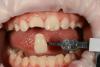

Diamondus Опубликовано 17 января, 2013 Поделиться Опубликовано 17 января, 2013 Девочка 9 лет. Скол вследствие травмы. Апекальная часть не сформирована. Детский врач направила для изготовления металлической штампованной коронки. Сказала, что после формирования верхушки (после 12 лет) заменить на композитную реставрацию. А сейчас композитную реставрацию проводить нельзя, есть возможность получить пульпит. На дентин только стеклоиномер. Пробовал перекрывать дентин стеклоиномером, эмаль композитом. Но все выпадает. Решил поставить керамический винир без препарирования. Ваше мнение в данной ситуации? Ссылка на комментарий